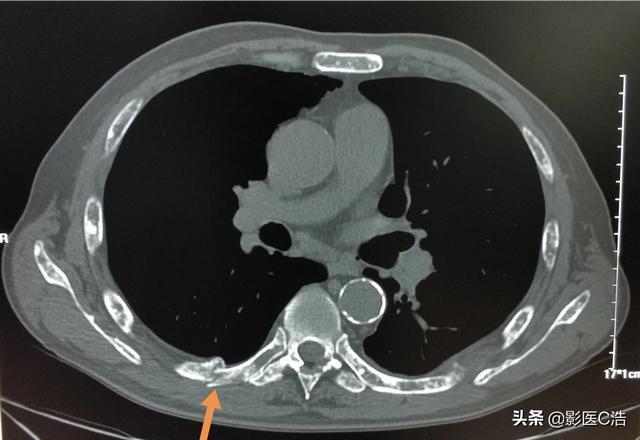

Des fractures pathologiques peuvent également se produire lorsque des métastases se développent dans l'os, généralement dans les côtes, parce que les métastases détruisent la structure normale de l'os, le rendant faible et susceptible de se fracturer lorsqu'une force externe est appliquée. Certaines métastases osseuses peuvent également se présenter sous la forme de masses de tissus mous autour de l'os, mais elles ne sont pas faciles à détecter car elles ne sont pas à la surface du corps. Fracture pathologique (flèches ci-dessous)